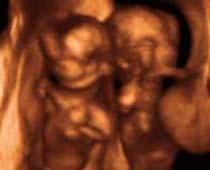

Clips vidéo 4D scan ultrason fœtal | Dr N Layyous

Clips vidéo 4D scan ultrason fœtal